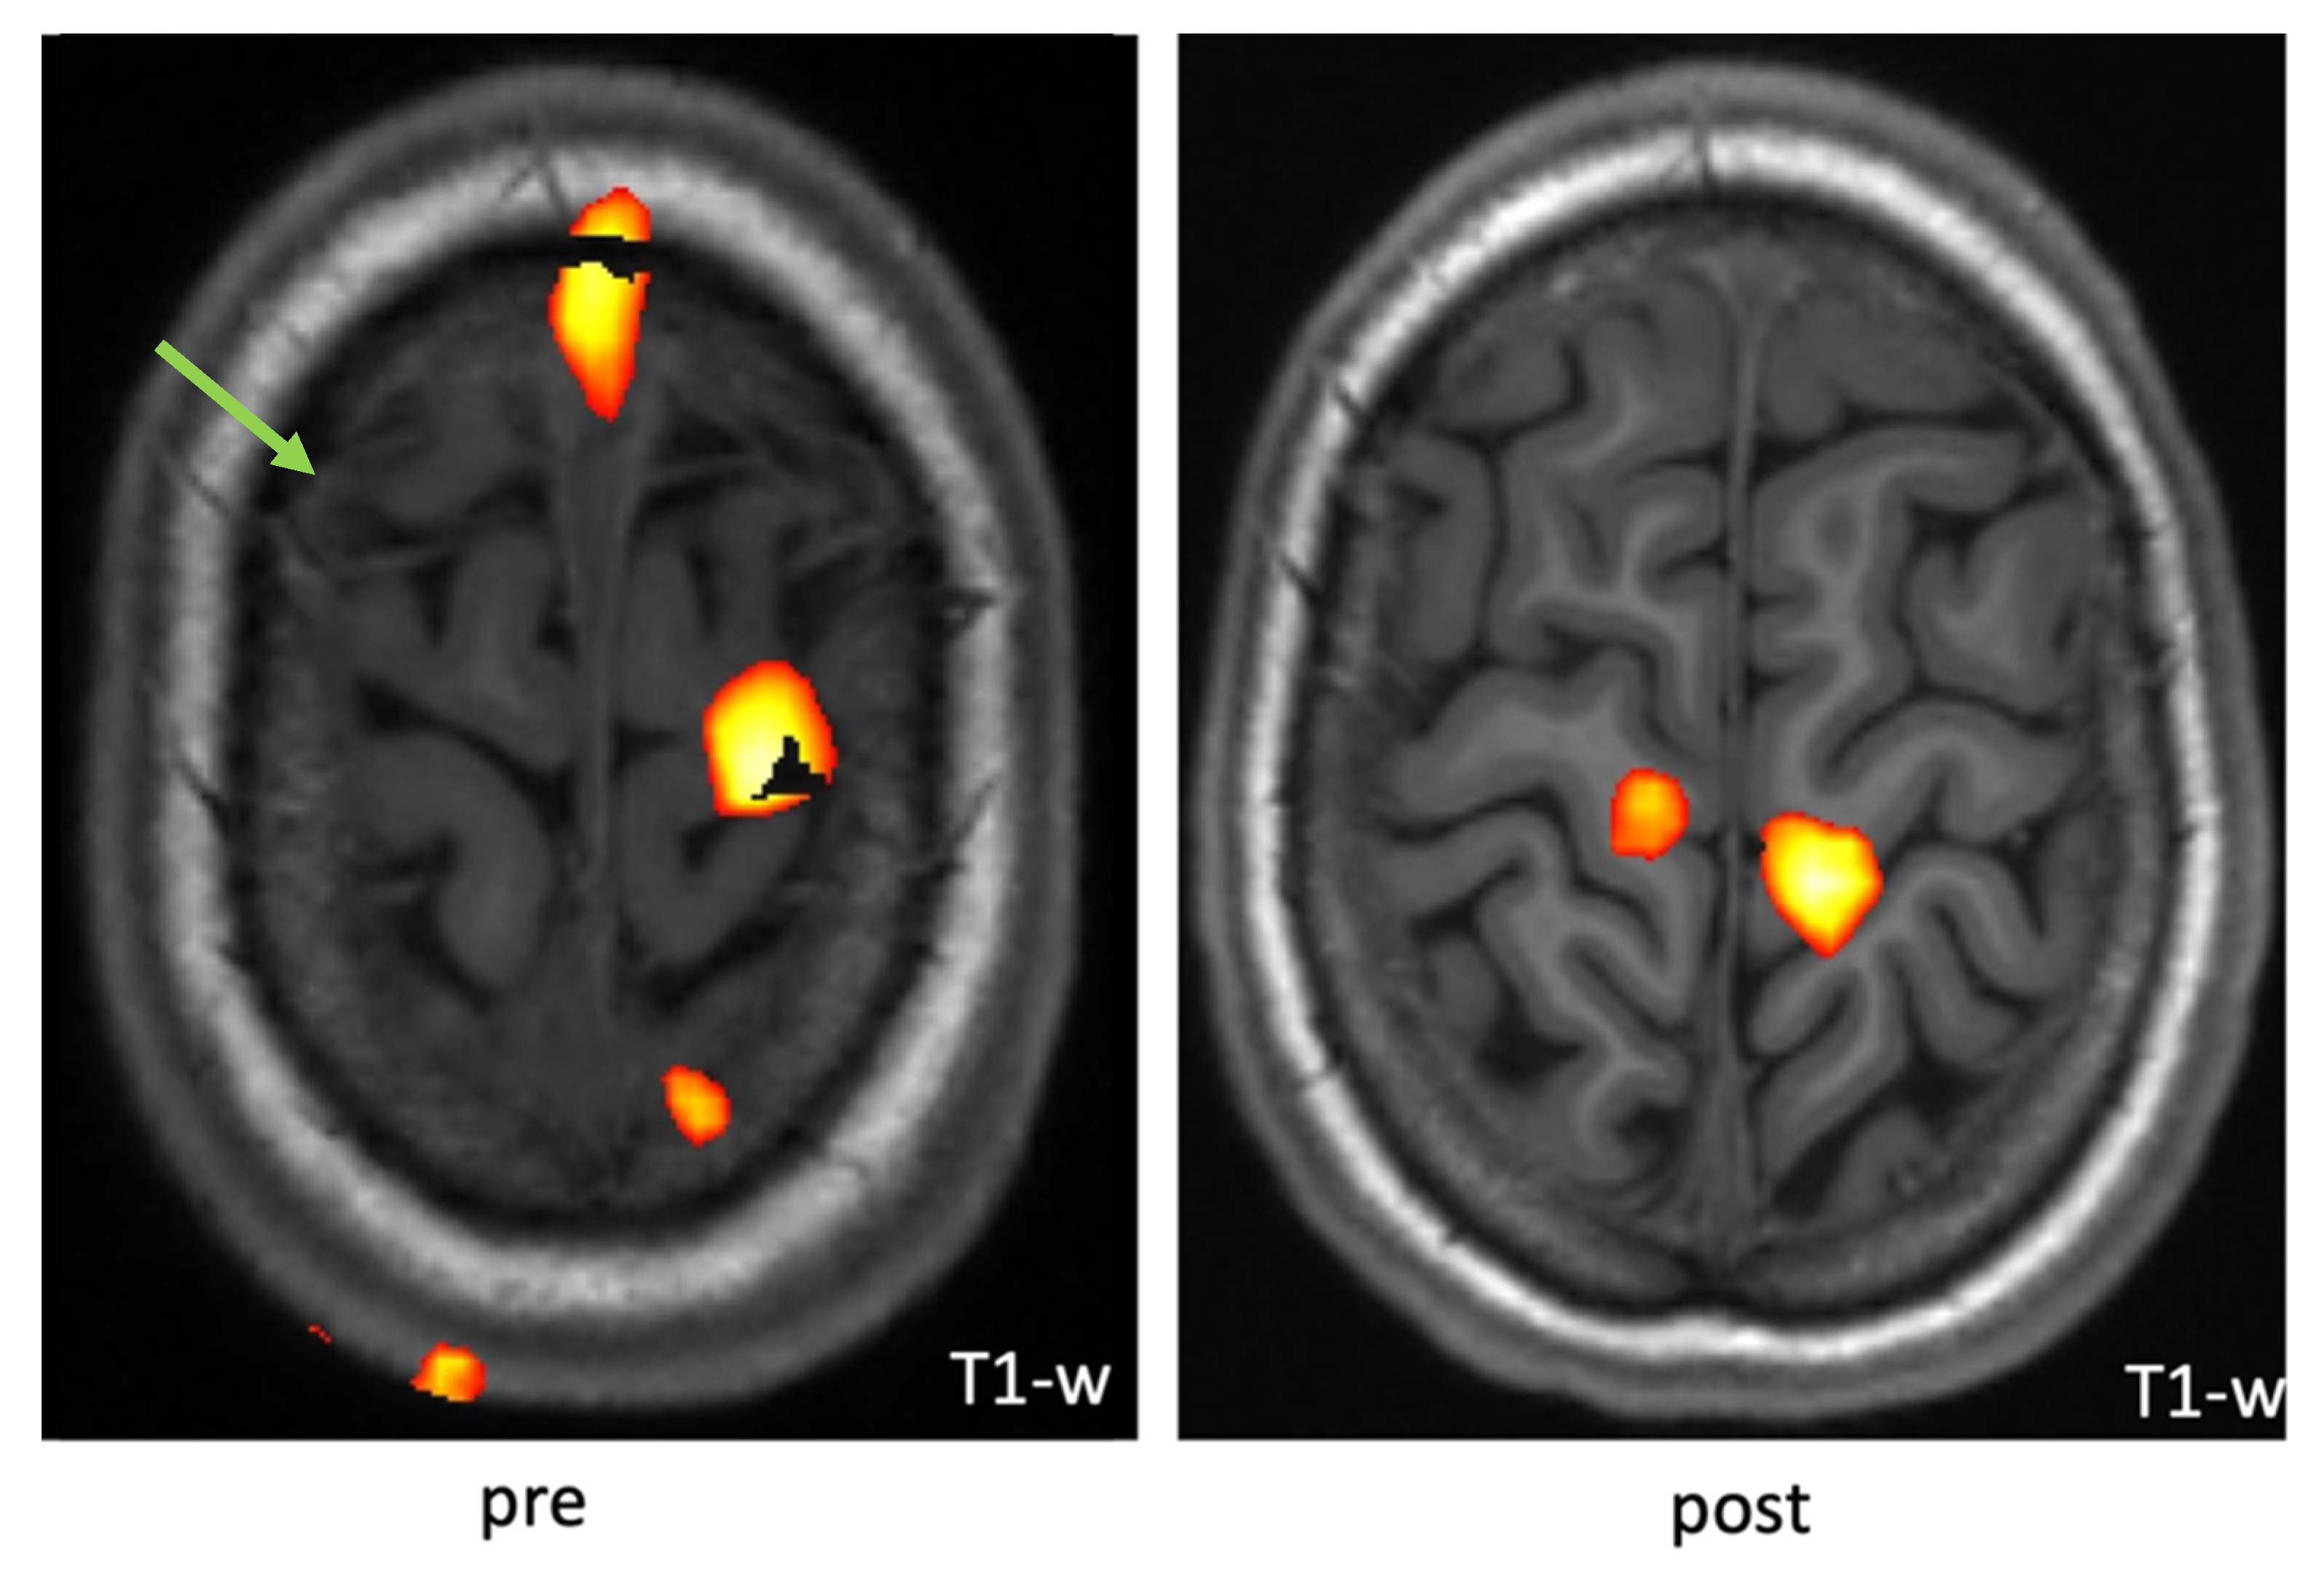

2.4. Functional Magnetic Resonance Imaging (fMRI)